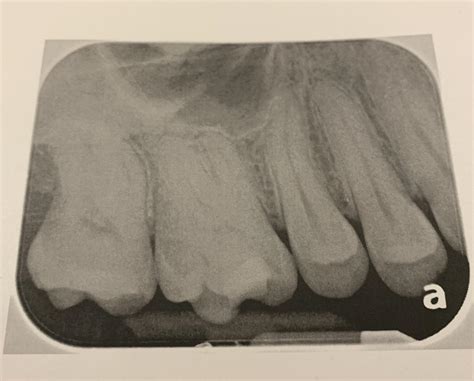

• Complex Anatomy: Sometimes, a tooth has extra canals that may have been missed during the initial treatment, allowing bacteria to remain and continue causing infection.

• Cracked Root: In some cases, a tooth may have a hairline fracture that is difficult to detect, which can cause ongoing pain even after the pulp is removed.

• RCT Radiograph